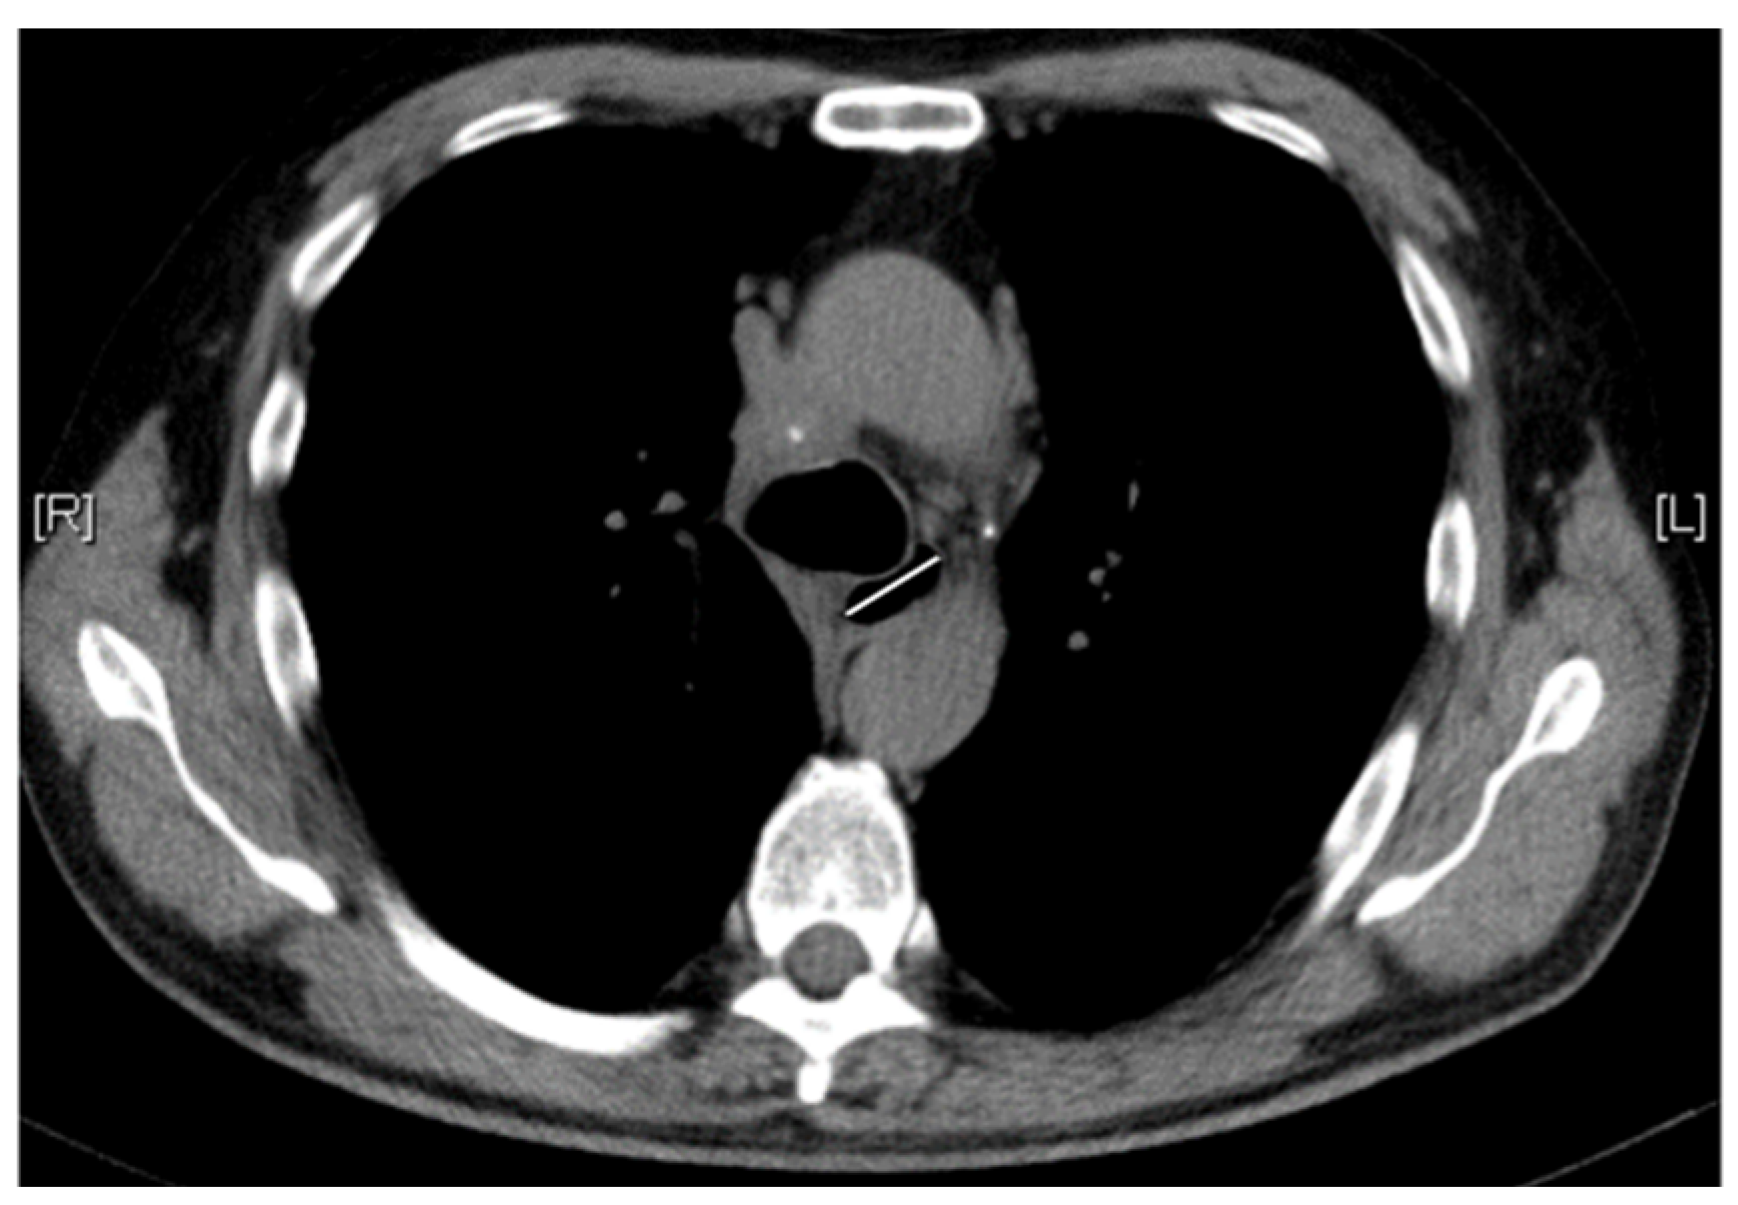

2.2. Esophageal Measurements on Chest CT Scan

| WED | 0.376 | 1.457 (1.206, 1.948) | <0.001 |